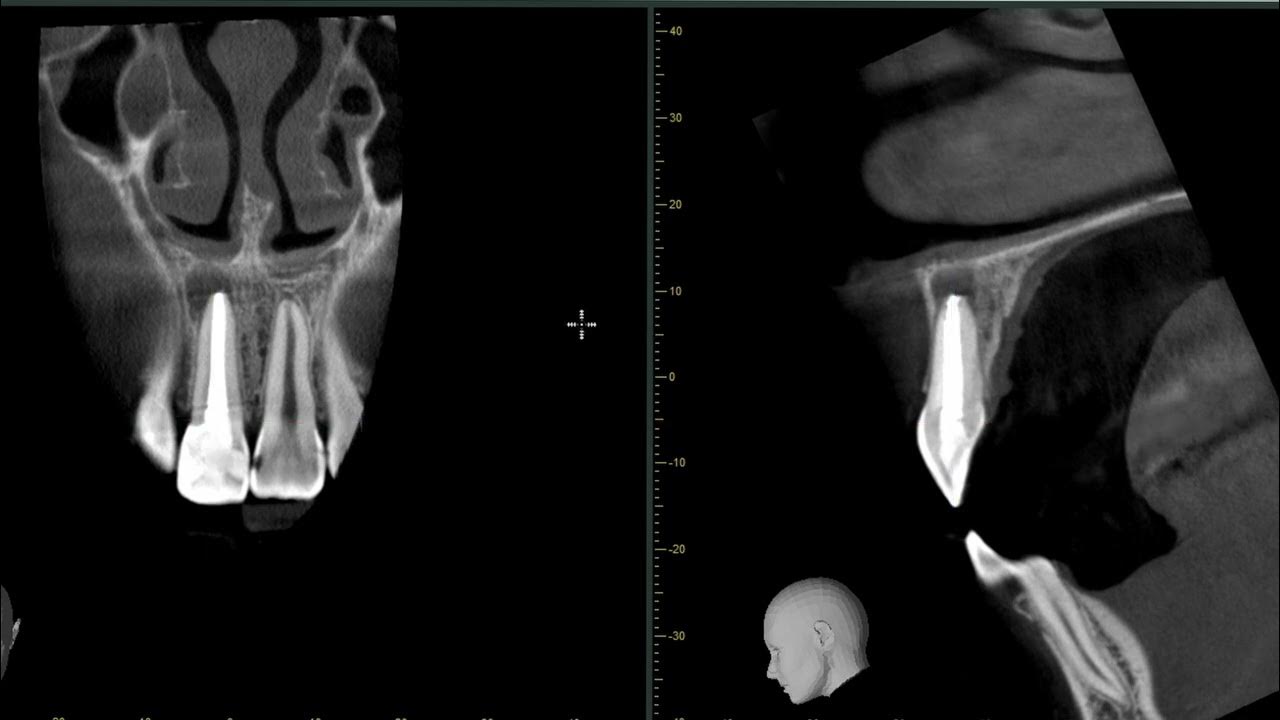

Просмотр зуба на КТ, как найти mb2